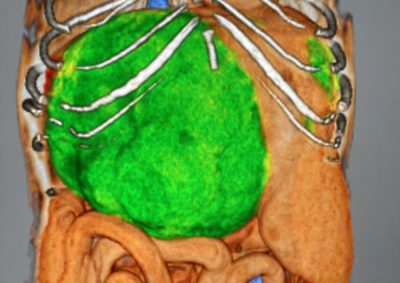

腫瘍外科 注意 ボタンをクリックした先に、治療中および手術中の画像が説明で使用されている場合がございます。 そのような画像に弱い方は閲覧なさらないようお願いいたします。 軟部組織外科腫瘍外科 肺葉切除術 腫瘍外科 胃の腫瘍 軟部組織外科腫瘍外科 大腸腺癌 腫瘍外科 肺葉切除術 腫瘍外科 肝葉切除術 腫瘍外科救急・集中治療 脾臓腫瘤破裂による腹腔内出血 腫瘍外科脳神経科 鼓室に発生した扁平上皮癌 軟部組織外科腫瘍外科救急・集… 脾臓破裂 軟部組織外科腫瘍外科救急・集… 出血性心タンポナーデに対する胸腔鏡下心膜切除術 腫瘍外科 前立腺癌を外科的に切除した犬の1例 腫瘍外科 Mott細胞分化を伴う腸管リンパ腫 Intestinal lymphoma with ... 腫瘍外科 肝細胞癌のチワワの1例 <1234567> 症例カテゴリー 放射線治療整形外科軟部組織外科脳神経外科内科腫瘍外科救急・集中治療リハビリテーション科腫瘍内科内視鏡科脳神経科呼吸器外科中医・漢方猫の腎移植循環器科